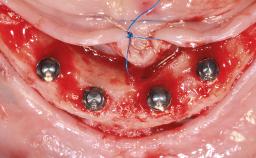

Mandibular Implant-Retained Overdenture on a CAD/CAM-Milled, Parallel-Walled CrCoMo Bar